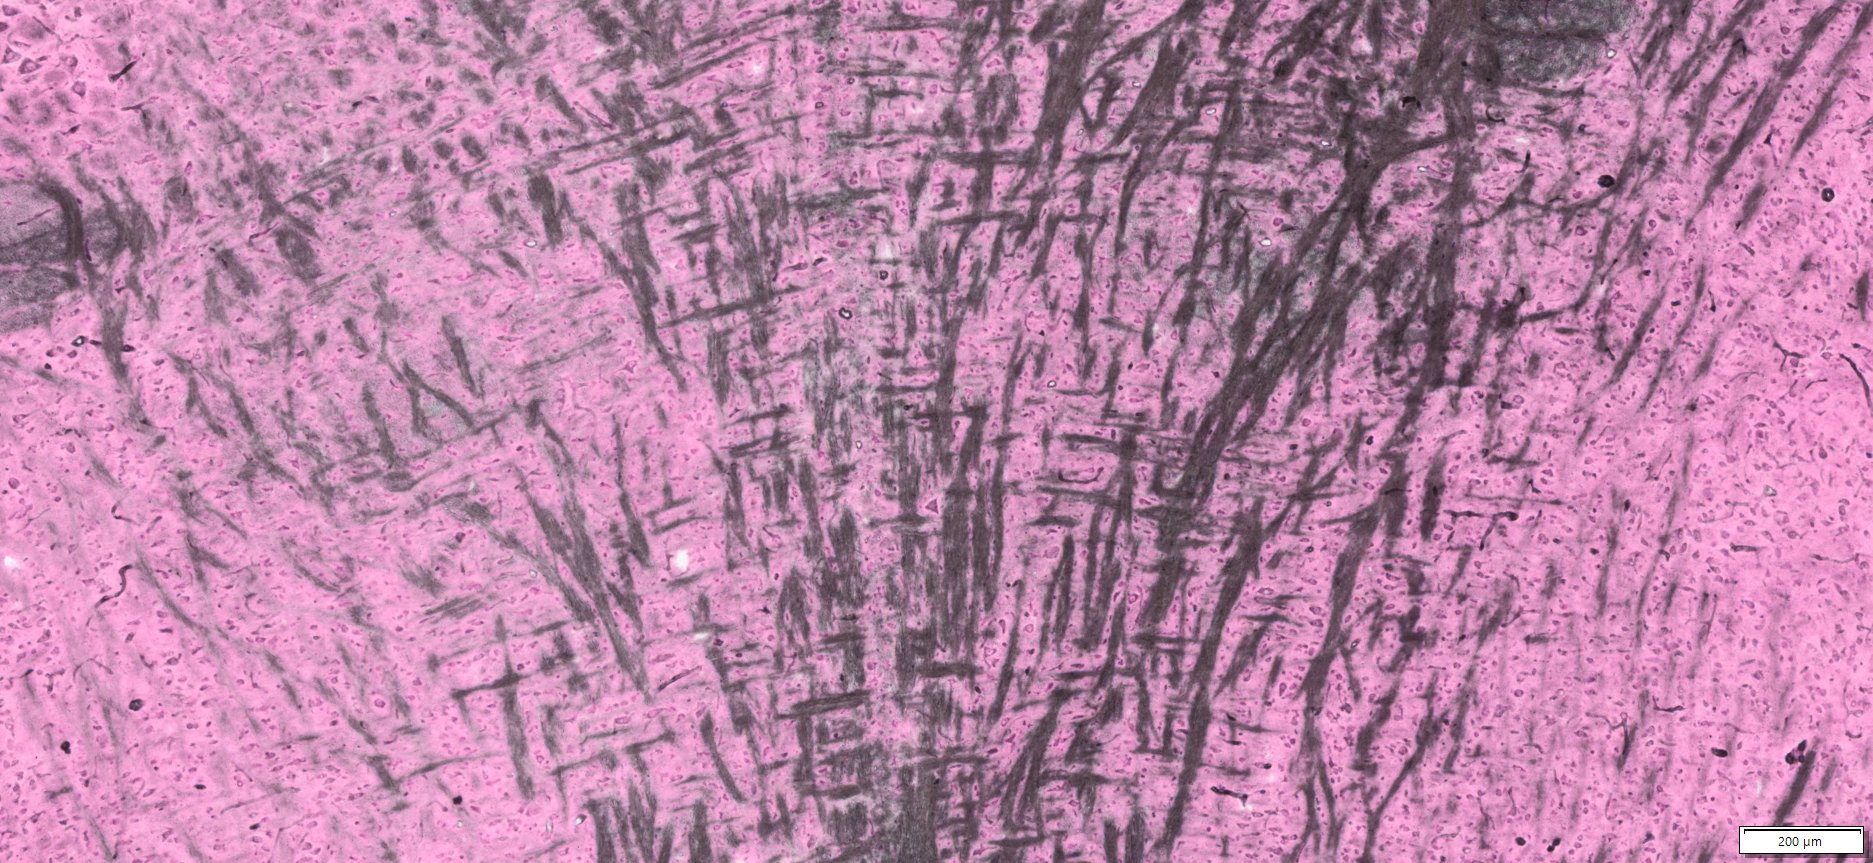

Expected Results

- Myelin and erythrocytes———–black

- Nuclei ———————————red

More Images